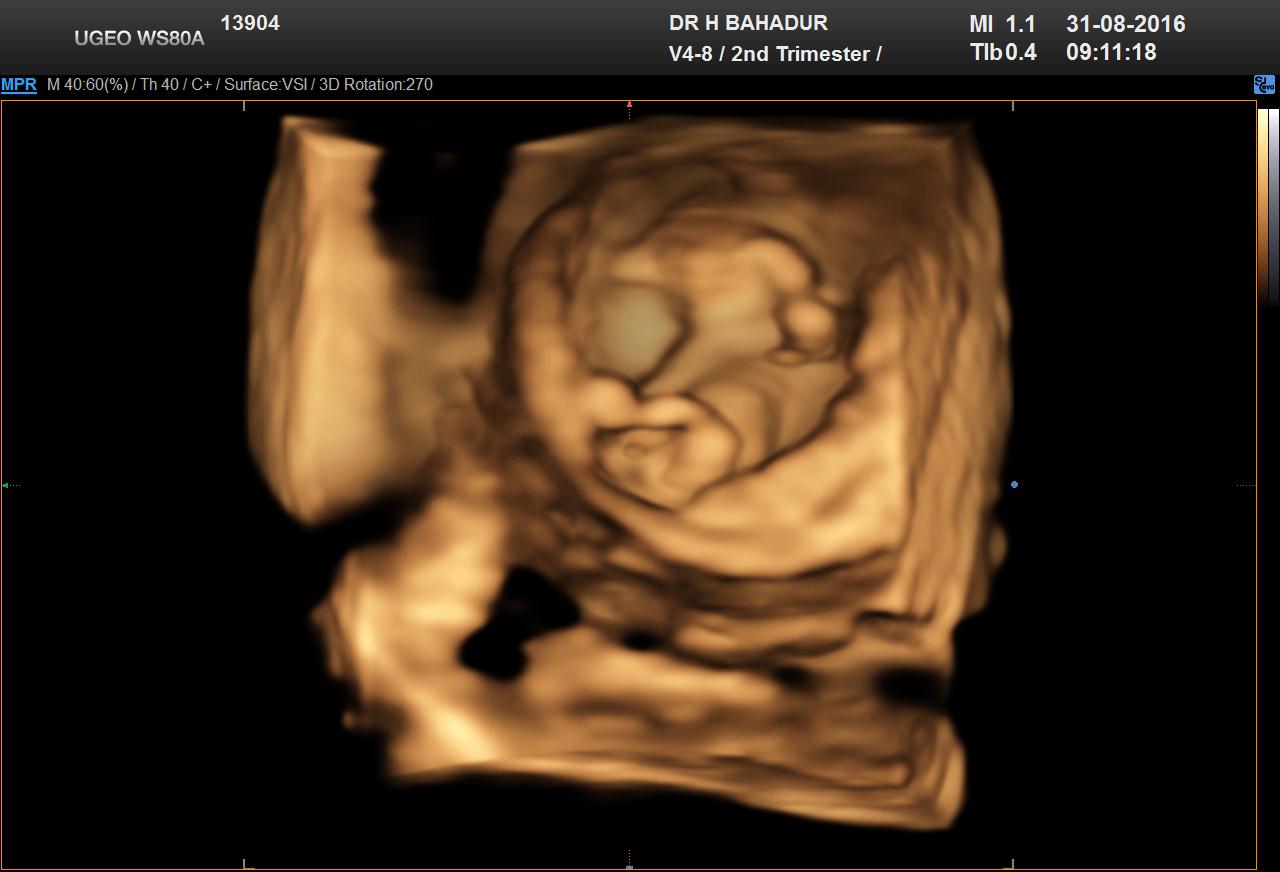

Hi everyone. Herw is my 12 week sonar. Really excited... can anyone determine my little blessings gender? I think boy but not 100% sure... Opinions???Attachment 32950Attachment 32951